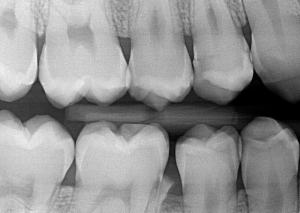

Интраорална кариес диагностика (Bitewing)

За направата на тази рентенография се използва техника, при която се захапва специален държач за рентгеновия филм или сензор, даваща възможност за визуализиране на горните и долни зъби в един образ. Този вид зъбни снимки визуализира коронките на премоларните и моларните зъби от едната страна на челюстите и се използва за кариесдиагностика в апроксималните части на зъбите, костна загуба или пародонтит.